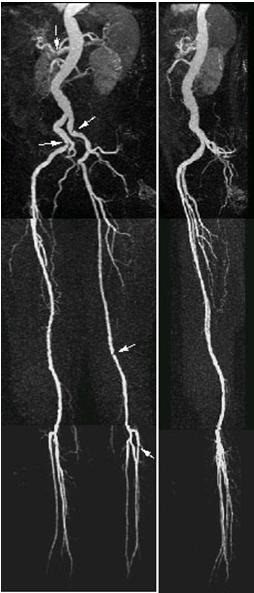

Figure 1. QuickSTEP lower extremity run-off